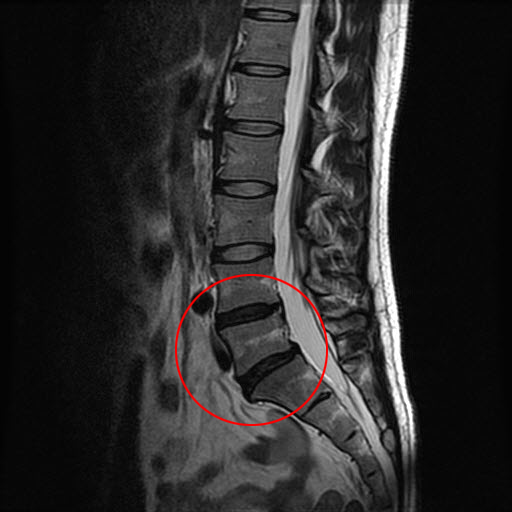

µð½ºÅ©³»ÀåÁõÀºµð½ºÅ© Á¶Á÷ÀÌ ÆÄ¿­µÇ¾î ÅëÁõÀ» ÀÏÀ¸Å°´Â Ç㸮µð½ºÅ©¿Í ´Þ¸® µð½ºÅ© ³»ºÎÀÇ º¯È­·Î »ý±â´Â ÁúȯÀ̾ Áø´ÜÀÌ ±î´Ù·Ó´Ù.µð½ºÅ©ÀÇ ¿ÜÀûÀÎ º¯ÇüÀ̳ª ÀÌÅ»ÀÌ ¾ø¾î¼­ ÀϹÝÀûÀÎ X¼± °Ë»ç, CT °Ë»ç µîÀ¸·Î´Â º¯È­¸¦ ã¾Æ³»±â ¾î·Æ°í MRI °Ë»ç ½Ã ¹®Á¦°¡»ý±ä µð½ºÅ©°¡ °ËÀº»öÀ¸·Î º¸ÀÌ´Â °ÍÀ¸·Î È®ÀÎÇÒ ¼ö ÀÖ´Ù.

ôÃß°üÀý ÅëÁõÄ¡·á±¸·Î¿¹½ºº´¿ø Â÷±â¿ë ¿øÀåÀº "º¸Åë ¿Ü»ó ÈÄ ÃÖ¼Ò ÀÏÁÖÀÏÀº Áö³ª¾ß µð½ºÅ©°¡ °ËÀº»öÀ¸·Î ³ªÅ¸³ª¹Ç·Î±³Åë»ç°í µî ºÎ»ó Á÷ÈÄ ÅëÁõÀÌ ¾ø´Ù°í ³Ñ±âÁö ¸»°í °æ°ú¸¦ ÁöÄѺ» µÚ¿¡ ÅëÁõÀÌ ÀÖÀ¸¸é MRI¸¦ Âï¾îº¸´Â°ÍÀÌ ÁÁ´Ù"°í ¸»Çß´Ù.